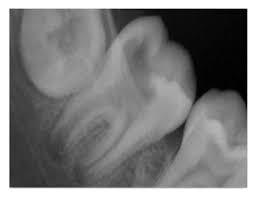

طفل جاى مع والدته بيشتكى من permanent tooth و عملت x-ray لقيته open apex

2-working length determination

و ناخد بالنا أن احنا هنحدد الطول باستخدام ال radiograph مش باستخدام ال apex locator